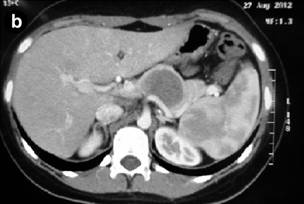

Computed Tomography (CT) of the Abdomen

CT of the abdomen (Figures 2) can identify a circumscribed lesion, usually single, encapsulated, with evidences of internal hemorrhage with tomographic heterogeneous aspects due to the presence of solid and cystic components in different amounts and predominance [1, 15, 16, 17]. Thus, the lesion can consist just of solid components and it can pass through the mixed or solid-cystic form (most common general tomographic presentation) and reach the purely cystic aspect [1, 15, 16, 17]. According to studies by Hu S et al. [16] and Park MJ et al. [15], there is different prevalence between the types of tomographic presentations of pancreatic SPN lesions regarding gender. Thus, the solid-cystic form is the most frequent in women and in men, the form consisting just of solid components prevails [15, 16]. Still, the contrast or understrapper (hyper-density of the image shown in the CT) will be stronger if the amount of existing solid component in the lesion is bigger [1, 15, 16, 17]. Other features able to be evaluated and identified through the CT are: calcification in the capsule, periphery or in the center of the lesion [1, 15, 16, 17]; pancreatic parenchyma around the lesion with normal aspect associated with the non-dilated pancreatic and/or bile ducts [1, 15, 16, 17]; and invasions of vascular structures and neighbor organs, as well as metastases [4, 5, 7]. Finally, the vascularization of the tumor itself is often avascular or little to modestly hyper-vascular, but it is rarely seen [5]. Yet, it is worth talking about the role played by PET-CT when handling pancreatic NSP patients. Unfortunately, there are just a few studies about the use of PET-CT to evaluate these patients. Thus, the few existing studies on this theme are retrospectives with small casuistic [21]. We highlight the uni-institutional retrospective study by Kim Y, et al. [21] which considers the recommendation of PET-CT to evaluate pancreatic NSP patients in order to identify the subtle metastases, especially when it assesses patients with a tumor formed by predominantly solid components.

|

Figure 2. a. Abdominal computerized tomography showing the SPN in the pancreatic head in Case #8. b. Abdominal computerized tomography after body-tail pancreatectomy with splenectomy for SPN (Case #7). |

Sixty percent (60%) of our patients were diagnosed with SPN of with the use CT and MRI scans of the abdomen (Table 2 and Figures 2a and 3). All the patients in our cohort had normal values of the following laboratory studies: complete blood count, coagulation panel (Prothrombin time; International normalized ratio; Partial thromboplastin time; Number of platelets; Bleeding time) amylase, serum creatinine, blood urea, serum albumin, liver profile and also had normal pre-operative tumor markers (like CEA and CA 19.9). The anatomic and pathological examination corroborated the diagnosis of SPN in 90% of the cases. Immunohistochemical studies were necessary to get the final diagnostic confirmation in only one case.